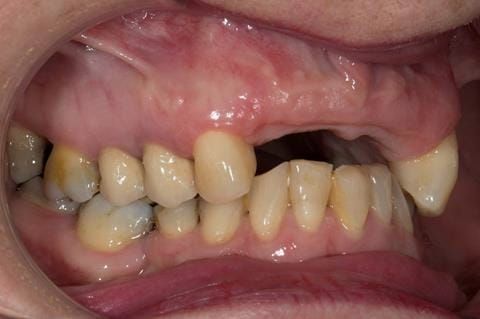

- UR2 peri-radicular periodontitis with a peri-radicular area on the root apex. Retrograde amalgam filling from a previous apicectomy. No visible root canal or root canal filling. Large circumferential marginal gap between the crown and tooth. Large post and core present. Very little tooth structure remaining resulting in a fragile tooth with increased potential for fracture.

- UR1 peri-radicular periodontitis with a small peri-radicular area on the root apex with wide blunderbuss apex. Radio-opaque root canal filling present approximately 3 mm short of the radiographic apex. Large circumferential marginal gap between the crown and tooth. Large post and core present. Very little tooth structure remaining resulting in a fragile tooth with increased potential for fracture.

- UL1 peri-radicular periodontitis with a peri-radicular area on the root apex. Retrograde amalgam filling from a previous apicectomy. Visible root canal space with no sign of root canal filling. Large circumferential marginal gap between the crown and tooth. Large post and core present. Very little tooth structure remaining resulting in a fragile tooth with increased potential for fracture.

- UL2 peri-radicular periodontitis with a peri-radicular area on the root apex. No visible root canal or root canal filling. Large circumferential marginal gap between the crown and tooth. Large post and core present. Very little tooth structure remaining resulting in a fragile tooth with increased potential for fracture.

- High smile line showing gum above gingival zeniths of upper front teeth when smiling. Aesthetic failure of the upper four incisors with inflammation of the gingivae and mis-match of the gingival zenith levels.

- Other than the maxillary incisors the remaining dentition was in marginally better condition being moderately to heavily restored. Many will probably require replacement and restoration from time to time mainly from wear and tear owing to occlusal forces.